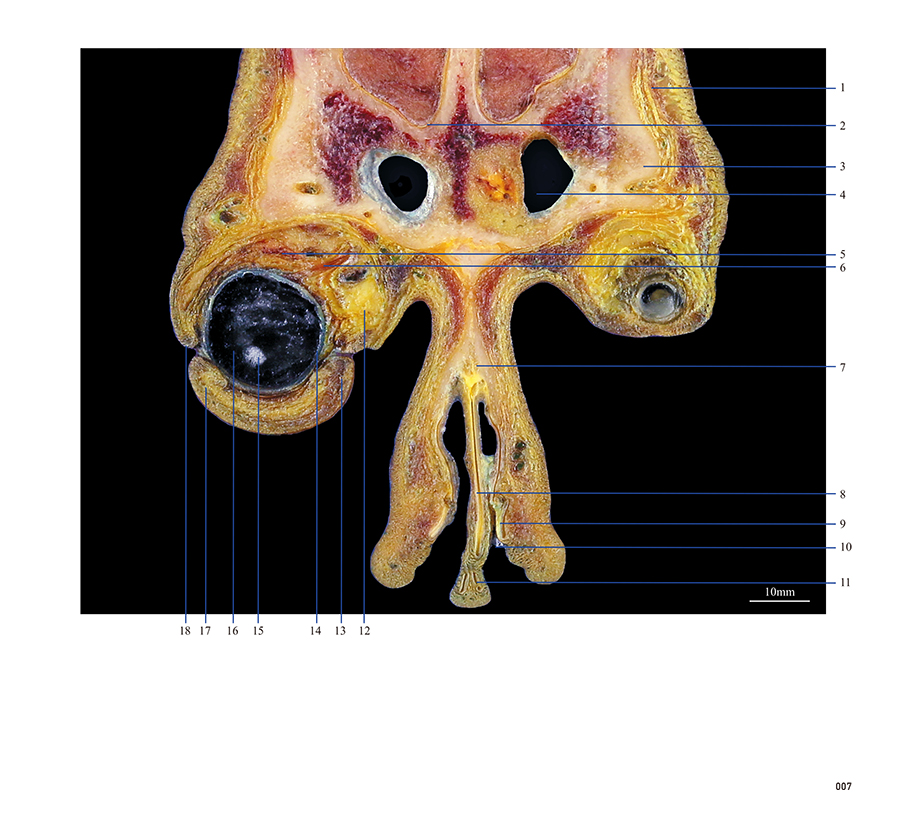

本书从数据集每隔1.2mm选取一幅图像,截取眼、耳、鼻及毗邻颅底的局部区域图像,共112幅图像。同时配以相应部位的CT图像对照。本书特色是断层解剖图利用数字图像处理技术优势,放大并清晰展示眼、耳、鼻及毗邻颅底断面的局部区域结构,组织色泽真实,甚至能够清晰显示肌肉纹理、筋膜纹路等细节结构,图像质量高于美国《人体断层解剖学彩色图谱》(引进版)类似图谱图像质量。对眼科、耳鼻咽喉科和神经内外科医生理解相关解剖结构有较大帮助。